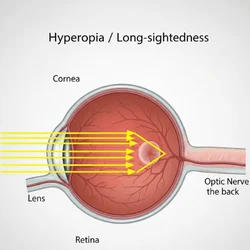

Long sightedness

Yes, in some cases a squint (strabismus) can be improved or corrected with eyeglasses. This usually works when the squint is caused by a refractive error, such as farsightedness (hyperopia). Glasses help the eyes focus properly, which can reduce or even eliminate the eye misalignment.